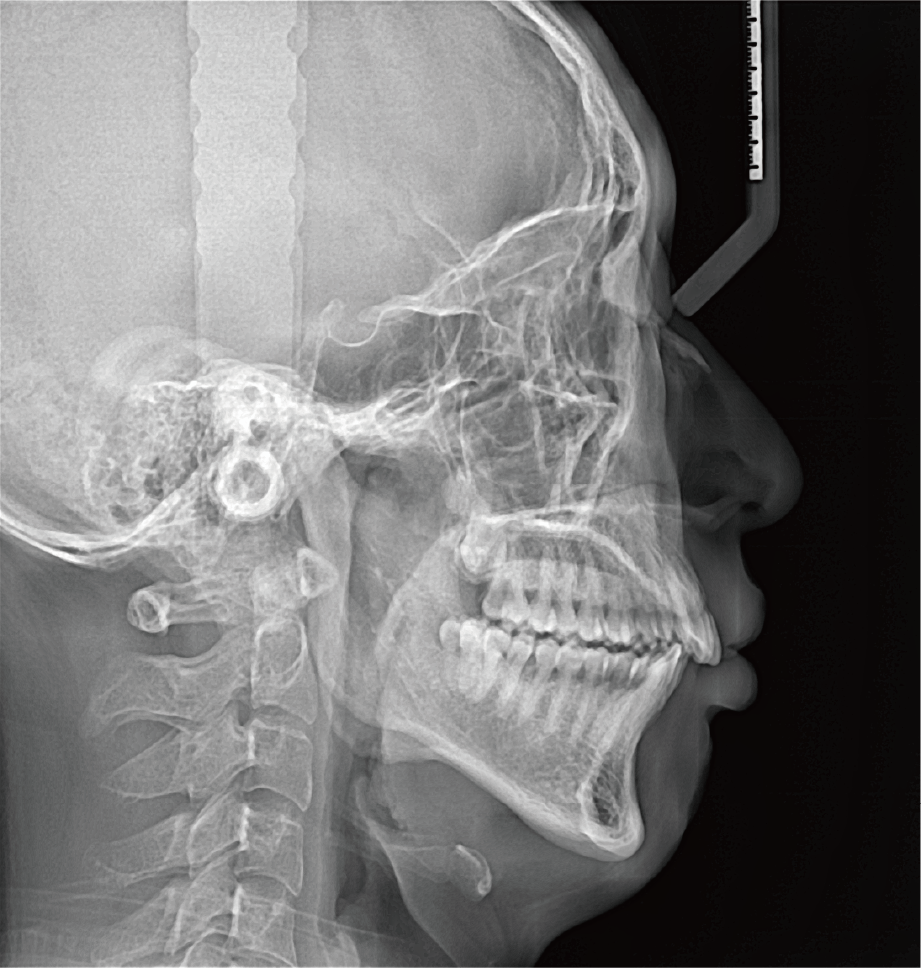

标配专业正畸软件

支持自动描点功能

精准定位

临床样片